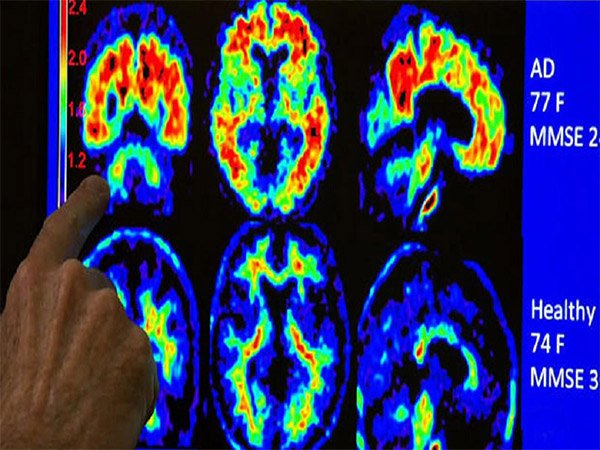

تهران – ایرنا – محققان دانشگاه توهوکوی ژاپن «Tohoku» با استفاده از امواج مافوق صوتی موفق به درمان اختلال شناختی در موش های مبتلا به دمانس شدند.به گزارش گروه اخبار علمی ایرنا از پایگاه خبری ساینس دیلی، محققان تحقیقات را با دو گروه از موش ها آغاز کردند. اولین گروه تحت عمل جراحی قرار گرفتند و جریان خون به مغز آنان کاهش یافت و اثرات دمانس عروقی شبیه سازی شد. گروه دوم به گونه ای مهندسی شدند که شرایطی شبیه به آلزایمر داشتند.محققان هر دو گروه را هر روز سه بار به مدت ۲۰ دقیقه تحت امواج مافوق صوت کم شدت (LIPUS) قرار دادند. پس از اتمام دوره درمان دریافتند هر دو گروه بهبود قابل ملاحظه ای در عملکرد شناختی داشتند. مطالعات بیشتر نشان داد درمان باعث افزایش بیان آنزیمی شده است که در تشکیل رگ های خونی نقش دارد. از طرفی این مطالعه نشان می دهد درمان (LIPUS) باعث افزایش پروتئینی شده است که در رشد و نجات سلول های عصبی نقش دارد. این روش کاملا غیر تهاجمی در بازیابی حافظه موش ها نقش موثری داشته است.این روش می تواند بدون نیاز به هرگونه عمل جراحی و بیهوشی برای سالمندان مبتلا به زوال عقل موثر باشد.نتایج این مطالعه در نشریه Brain Stimulation منتشر شده است.